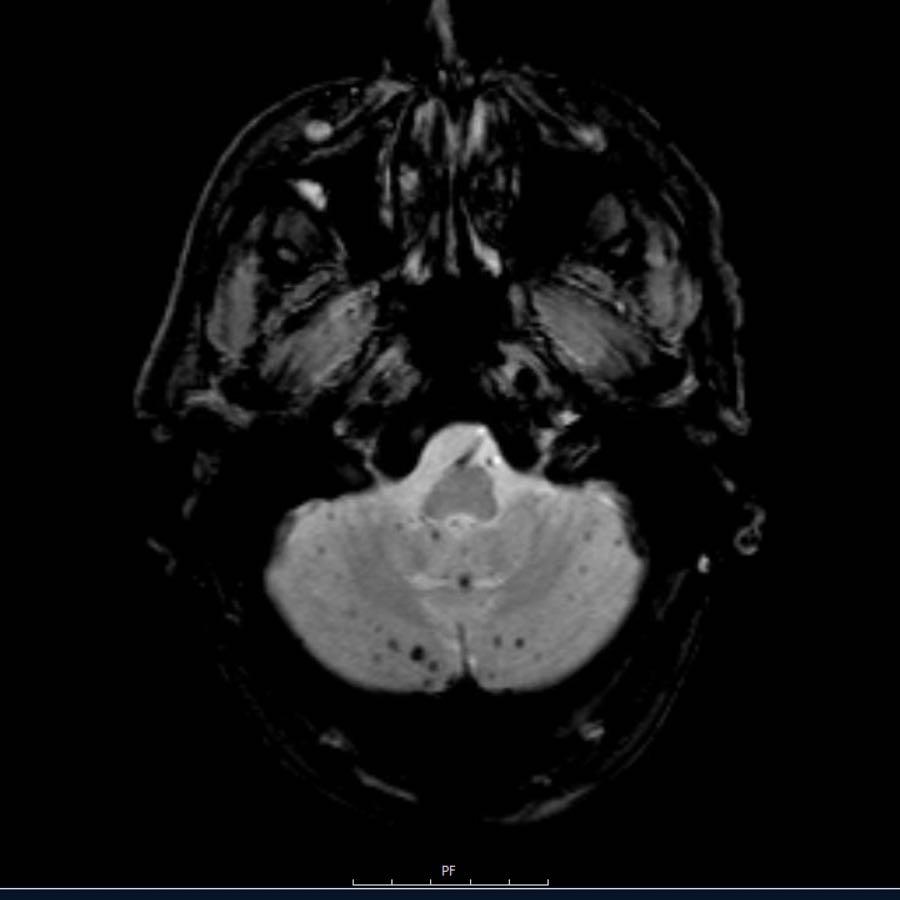

Bệnh nhân này nhập viện với xuất huyết tiểu não.

Các hình ảnh chuỗi xung gradient echo cho thấy nhiều vi xuất huyết.

Đây có thể là hậu quả của tăng huyết áp lâu năm do vị trí trung tâm của một số vi xuất huyết.